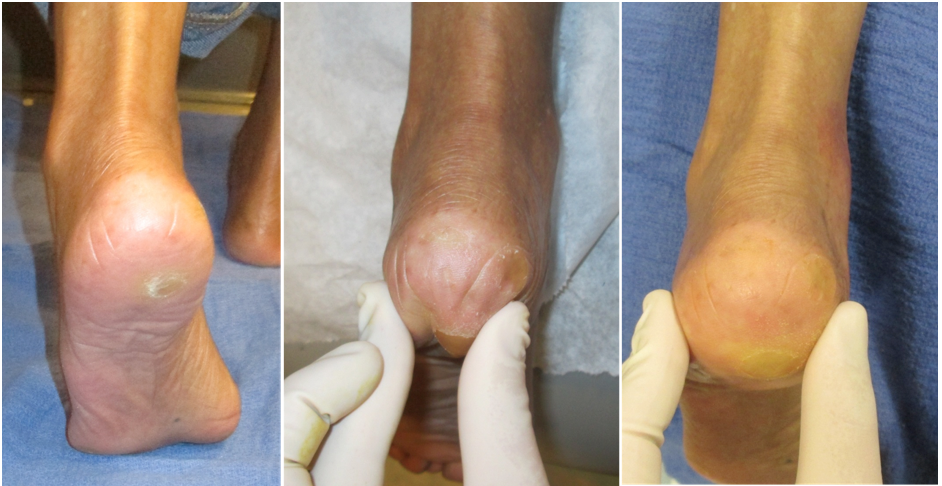

Fat pad repositioning and correction for metatarsophalangeal joint extension A Fat pad

The bottom of your feet would look weird, but nobody cares about feet aesthetics unless you're a mentally ill foot fetishist.

The 2nd idea would be a fat graft to your whole bottom foot. This would do the same thing as an implant, except it would be using your own fat to add extra cushion and therefore height to your bottom feet.

Autologous Fat Grafting For Pedal Fat Atrophy

If fat grafting can increase the size of your ass or chin, then it should be able to increase the size of your bottom feet.

Only flaw is again uglier bottom feet.

I would predict 1 inch of height could be added for the implant without looking uncanny, and 0.5 inch for the fat graft.